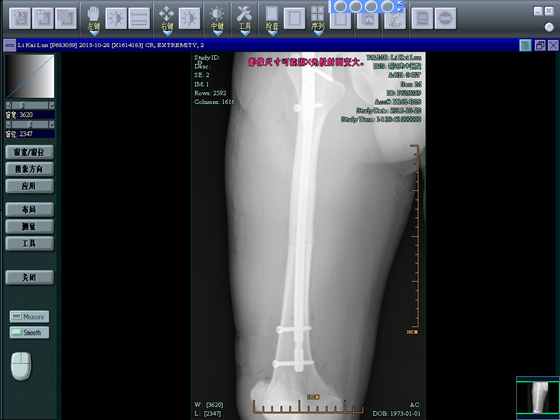

附录:病例1

李**,男,42岁,工地干活时被钢管砸伤右大腿。

术前

术后3月差10天复查,行走自如。